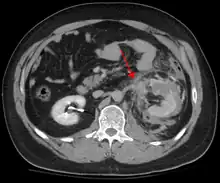

Blunt abdominal trauma

Blunt abdominal trauma (BAT) represents 75% of all blunt trauma and is the most common example of this injury.[3] 75% of BAT occurs in motor vehicle crashes,[4] in which rapid deceleration may propel the driver into the steering wheel, dashboard, or seatbelt,[5] causing contusions in less serious cases, or rupture of internal organs from briefly increased intraluminal pressure in the more serious, depending on the force applied. Initially, there may be few indications that serious internal abdominal injury has occurred, making assessment more challenging and requiring a high degree of clinical suspicion.[6]

When blunt abdominal trauma is complicated by 'internal injury,' the liver and spleen (see blunt splenic trauma) are most frequently involved, followed by the small intestine.[8]